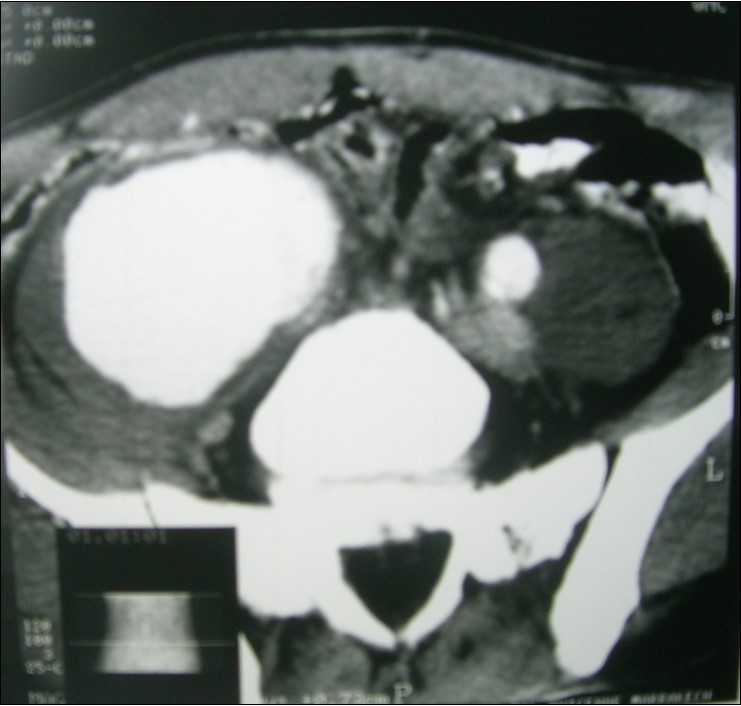

A45-year-old man, with no prior pathologic antecedent was admitted to the internal medicine department for a 3weeks history of abdominal pain. This symptom occurred in the context of apyrexia and 4 kilogram weight loss. Abdominal examination was a painful abdomen, distended. The skin examination noted painful genital andoral ulcers with pustlar lesions in the back. Angio CT scan revealed an aneurysm of the right common iliac artery (Figure 1).Artégraphie the lesion showed the same described above, showing the saccular aneurysm (Figure 2). He had no other aneurysmal localizations.

Figure 1.Angio CT scan revealed an aneurysm of the right common iliac artery.